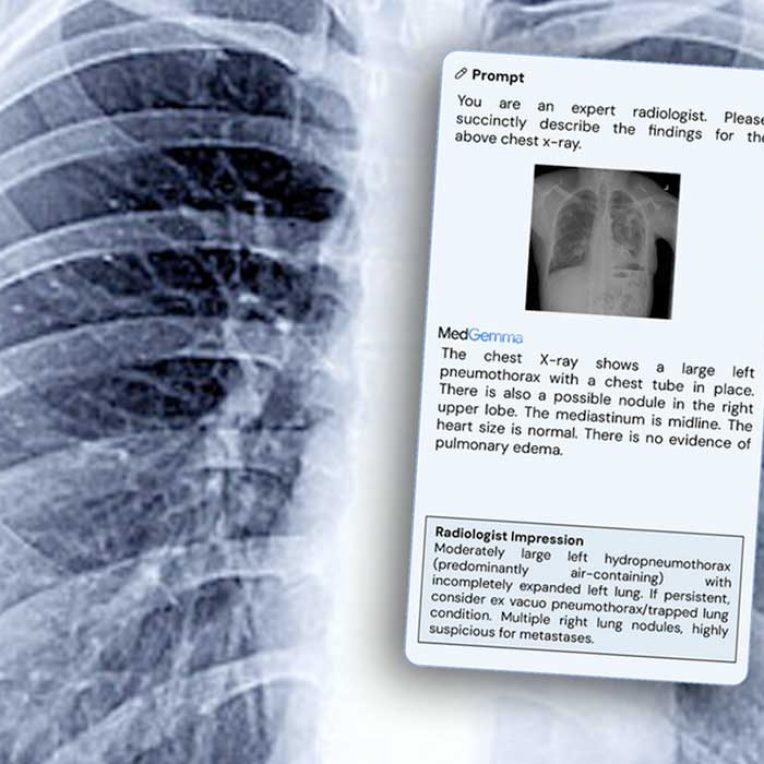

- Image Analysis & Reporting: A primary application is the generation of free-text reports from medical images. This is particularly useful in fields like radiology and pathology, where MedGemma can analyze an image (e.g., a chest X-ray) and generate a descriptive summary. It also excels at visual question answering (VQA), allowing clinicians to ask natural language questions about an image .

Furthermore, the power of MedGemma is amplified through fine-tuning. The technical report highlights that further training on specific subdomains can yield dramatic improvements. For instance, fine-tuning was shown to reduce errors in electronic health record information retrieval by 50% and achieve performance comparable to state-of-the-art specialized methods for tasks like pneumothorax classification . This demonstrates that MedGemma serves as a powerful and adaptable foundation for building highly accurate, specialized medical AI tools.